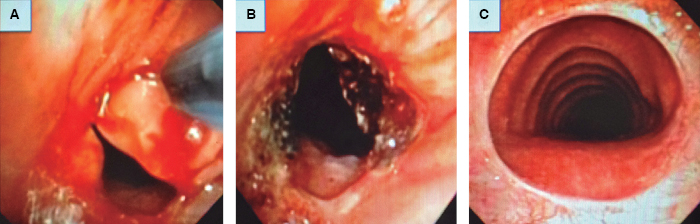

En 11 casos (55%) hubo mejoría satisfactoria del grado de oclusión y de los síntomas, de los cuales 5 presentaron mejoría después de la primera aplicación de CAP que se mantuvo durante el seguimiento, y 6 tuvieron mejoría sostenida después de 2-7 sesiones de CAP. De los pacientes que presentaron mejoría satisfactoria 5 recibieron dilatación traqueal en una o varias ocasiones. En 6 de 7 casos que presentaron mejoría satisfactoria fueron resecados granulomas. En 9 pacientes no hubo mejoría por no haber presentado reducción significativa del grado de oclusión; entre estos, 8 presentaron mejoría mínima de los síntomas o del grado de oclusión y en un caso de estenosis completa subglótica no hubo cambios. Las Figuras 1 y 2 muestran ejemplos de casos con evolución satisfactoria y no satisfactoria respectivamente.

Figura 1: A. Paciente que presentó evolución satisfactoria. La obstrucción fue diagnosticada 44 días después de ser sometido a traqueoplastia con anastomosis traqueotraqueal. B. Inicialmente se resecaron tres granulomas, además se extrajo un punto de sutura. C. El paciente fue sometido a cuatro sesiones con uso de argón plasma y la recuperación del lumen se mantuvo estable después de 10.5 meses.

Figura 2: A. Caso de evolución no satisfactoria de un paciente con estenosis subglótica compleja después de intubación, a quien le fue colocado un stent de silicón endotraqueal retirado posteriormente por formación de granulomas. B. Fue sometido a una sesión de coagulación con argón plasma y dilatación mecánica. C. Último control endoscópico a los siete meses de seguimiento.